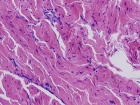

J.G. - 14 year old male c/o left posterior thigh mass for eight months. His mother noticed the mass, but no ecchymosis, after he fell while running hurdles. He complains of pain only when running long distances, and with prolonged pressure. It has decreased in size only minimally. No F/C.